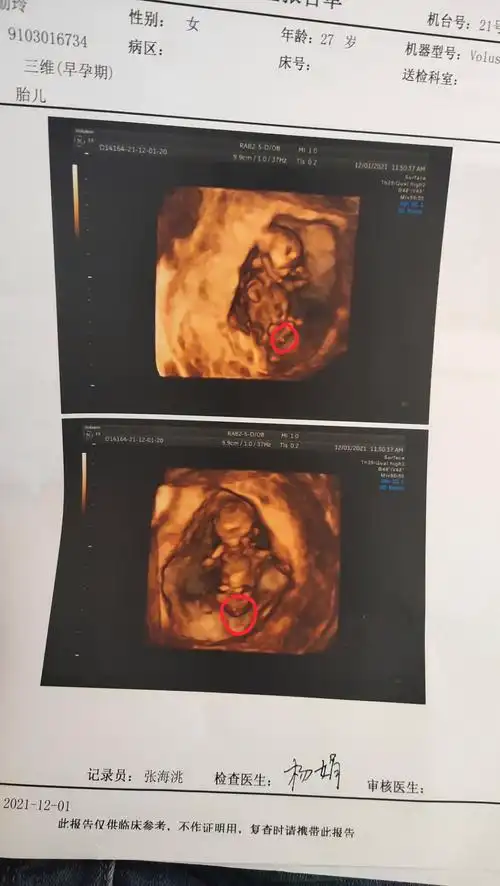

12月孕14周 5天宿州市妈妈网_mkpr5圈子同龄同城同院话题广场妈网态度